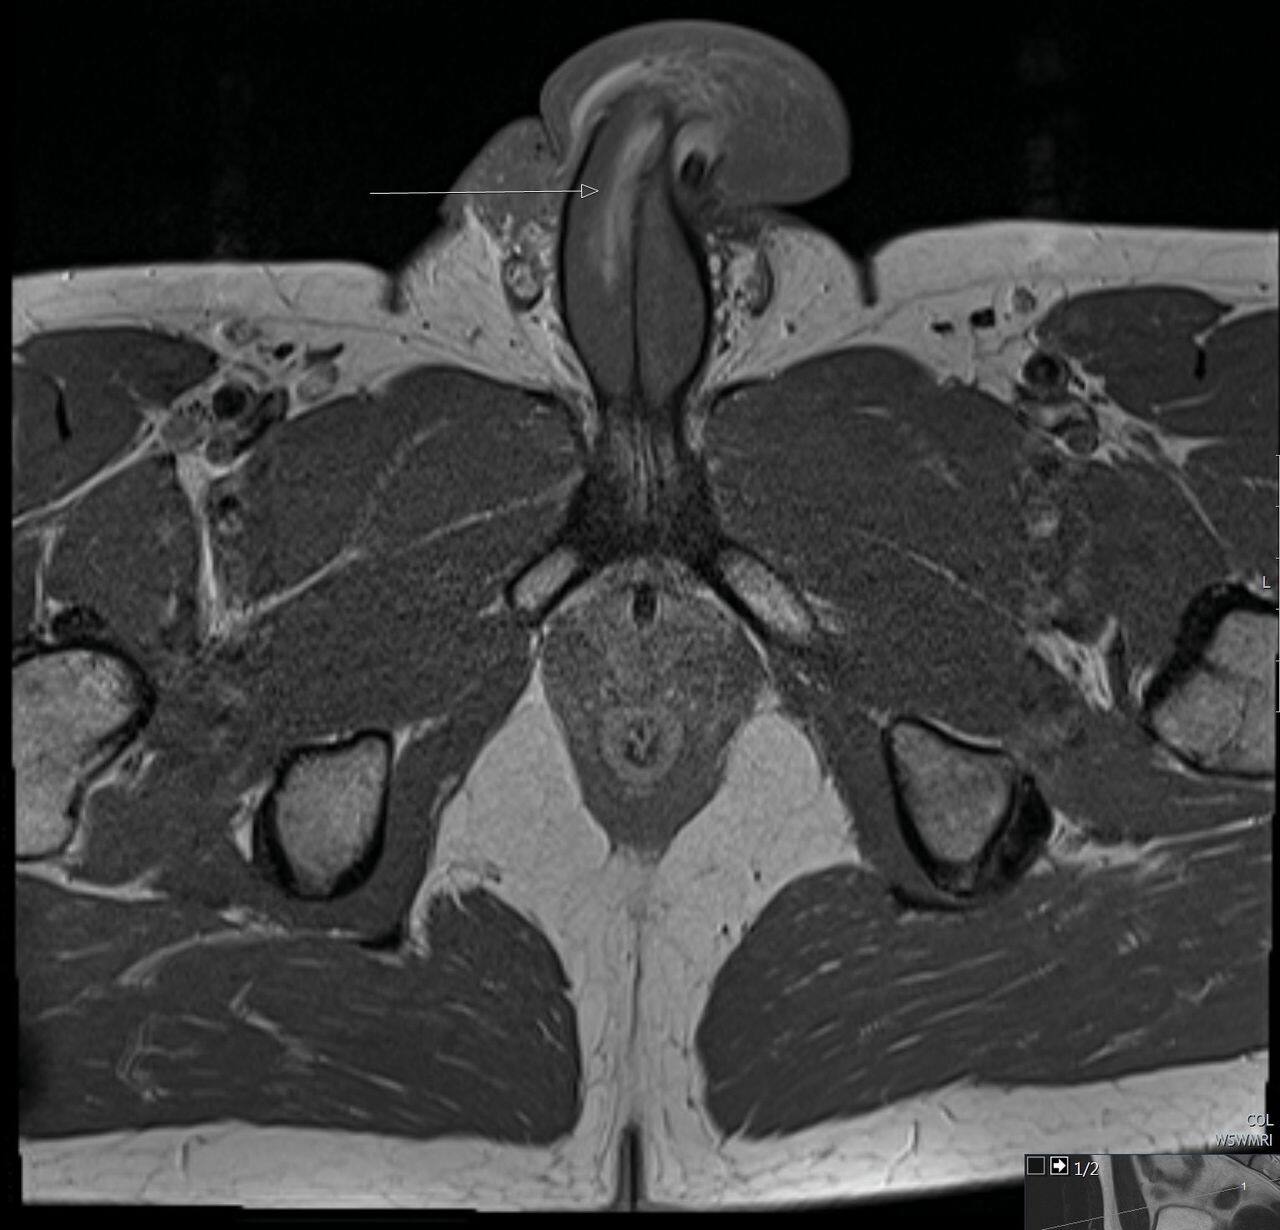

Il a cependant consulté un médecin qui, intrigué, a demandé à voir des images de résonance magnétique.

BMJ Case Reports

Ces dernières ont fait la preuve que l’homme avait subi une déchirure longue de trois centimètres dans les tissus sur le côté droit de son organe mâle, dans le sens de la longueur, et non dans le sens de la largeur.

Malheureusement pour tous, en raison des contraintes liées à la COVID-19, les photographes médicaux n’ont pas pu immortaliser la très rare fracture pénienne verticale du quadragénaire.